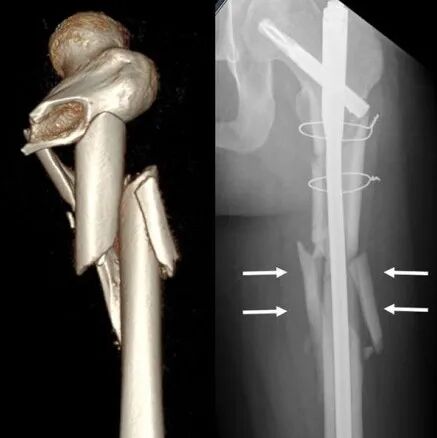

股骨粗隆下骨折占髋部骨折的10-34%,在解剖上,粗隆下骨折位于相对缺血的皮质骨区域,愈合较粗隆间骨折等松质骨骨折慢;生物力学上,该处承受应力较大,骨折后容易粉碎,尤其是内侧皮质。同时由于周围的肌肉强壮且负责,加剧了骨折移位和复位难度。

粗隆下骨折的内翻及前后成角畸形的发生率较高,后果严重。为此,有学者采用经皮阻挡钉技术,以纠正复位过程中的畸形复位,以恢复力线及股骨长度(原文分享至骨科青年群组)。

文章纳入25例在粗隆下骨折髓内钉固定中,采用阻挡钉病例,结合病例的术中透视情况,并认为在C臂机上透视移位超过1个皮质,认为复位不良,需要继续复位。

指征1:导针进针点位于大转子外侧。由于近端骨块在肌肉牵拉下出现内翻、内旋畸形,术中精准置入导针比较困难。如术中导针置入大转子间外侧,则近端骨块会出现内翻畸形,此时,需将导针进针点开口扩大,留出髓内钉内移空间,后在髓内钉可能置入方向的外侧,置入阻挡钉,纠正内翻畸形。